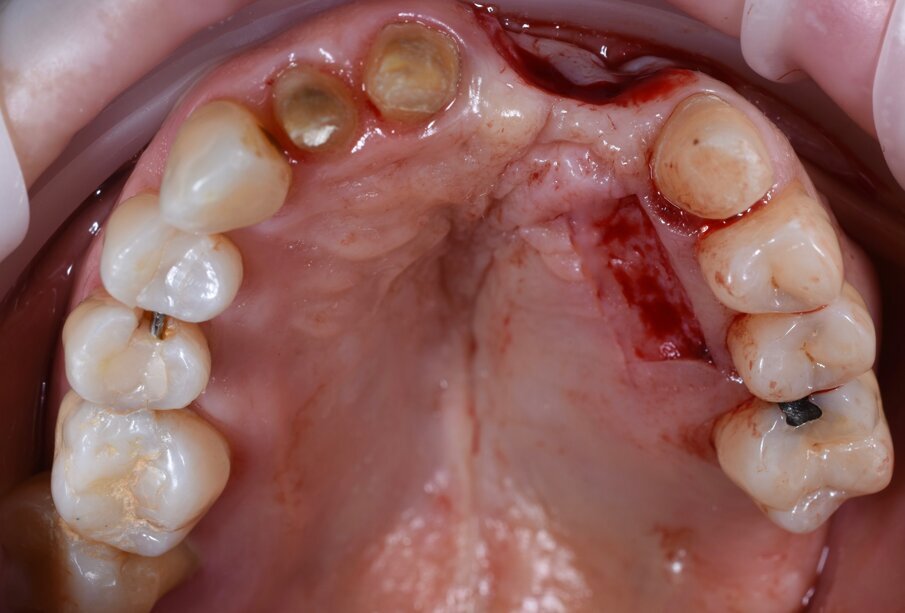

In questo articolo presentiamo un caso clinico che dimostra come il posizionamento improprio di un impianto può rendere impossibile la riabilitazione protesica, che richiede una nuova pianificazione chirurgica e riabilitativa per ottenere l’estetica desiderata. La paziente si presenta alla nostra osservazione con una riabilitazione protesica incongrua, con flangia in resina, a supporto dentale ed implantare, con la presenza di un impianto in posizione 2.1 vestibolarizzato e con l’emergenza nel fornice, in mucosa alveolare. Dalla valutazione della Tac si evince la posizione errata dell’impianto e la perdita consistente in senso trasversale della compagine ossea (Figg. 1, 2). Pertanto si opta per il seguente piano di trattamento che prevede: rimozione dell’impianto e preparazione protesica dell’elemento 2.3, confezionamento di un primo provvisorio a supporto dentale che servirà a guidare la guarigione dei tessuti (Figg. 3-7). A distanza di 4 mesi si procede a un innesto epitelio connettivale libero con prelievo dal palato per compensare il gap dei tessuti molli in senso trasversale, quindi viene ribasato il provvisorio in modo tale da favorire la guarigione dei tessuti (Figg. 8-11). A 9 mesi dalla maturazione dei tessuti si procede alla finalizzazione protesica fissa a supporto dentale (Figg. 12-14).

Fig. 3 - Rimozione del manufatto protesico che evidenzia la posizione errata dell’impianto in sede 2.1.

Fig. 4 - Visione occlusale dopo rimozione del manufatto protesico si noti la posizione errata dell’impianto.

Fig. 5 - Rimozione atraumatica dell’impianto con l’utilizzo dello svitatore.